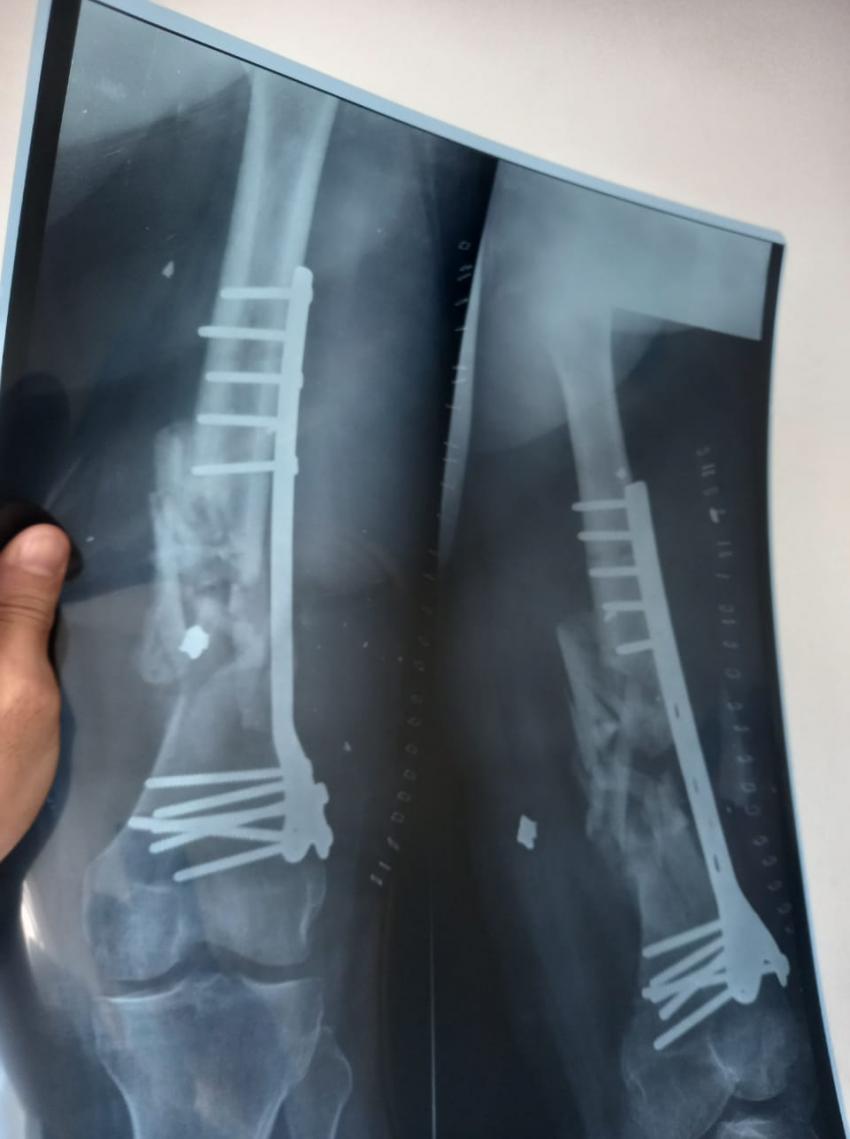

الراي نيوز - في إطار الجهود التي يقدمها المستشفى من أجل تقديم الخدمة والرعاية الطبية والإنسانية للأهل في قطاع غزة، أجرت طواقم المستشفى الميداني الأردني غزة /78 أمس السبت، عملية جراحية لتثبيت كسر مفتوح في أسفل عظم الفخذ (DISTAL FEMUR FX ORIF).

من جانبه بين طبيب جراحة العظام والمفاصل أن المريض كان يعاني من كسر مفتوح في أسفل عظم الفخذ اليمين مما أدى إلى تفتت العظم وتهتك الأنسجة المحيطة به نتيجة الإصابة التي تعرض لها المريض، وتم إجراء عملية جراحية وتركيب صفيحة معدنية وبراغي وإزالة المثبت الخارجي في المستشفى الميداني الأردني لكونه المستشفى الوحيد الذي ما زال مستمراً شمال القطاع.